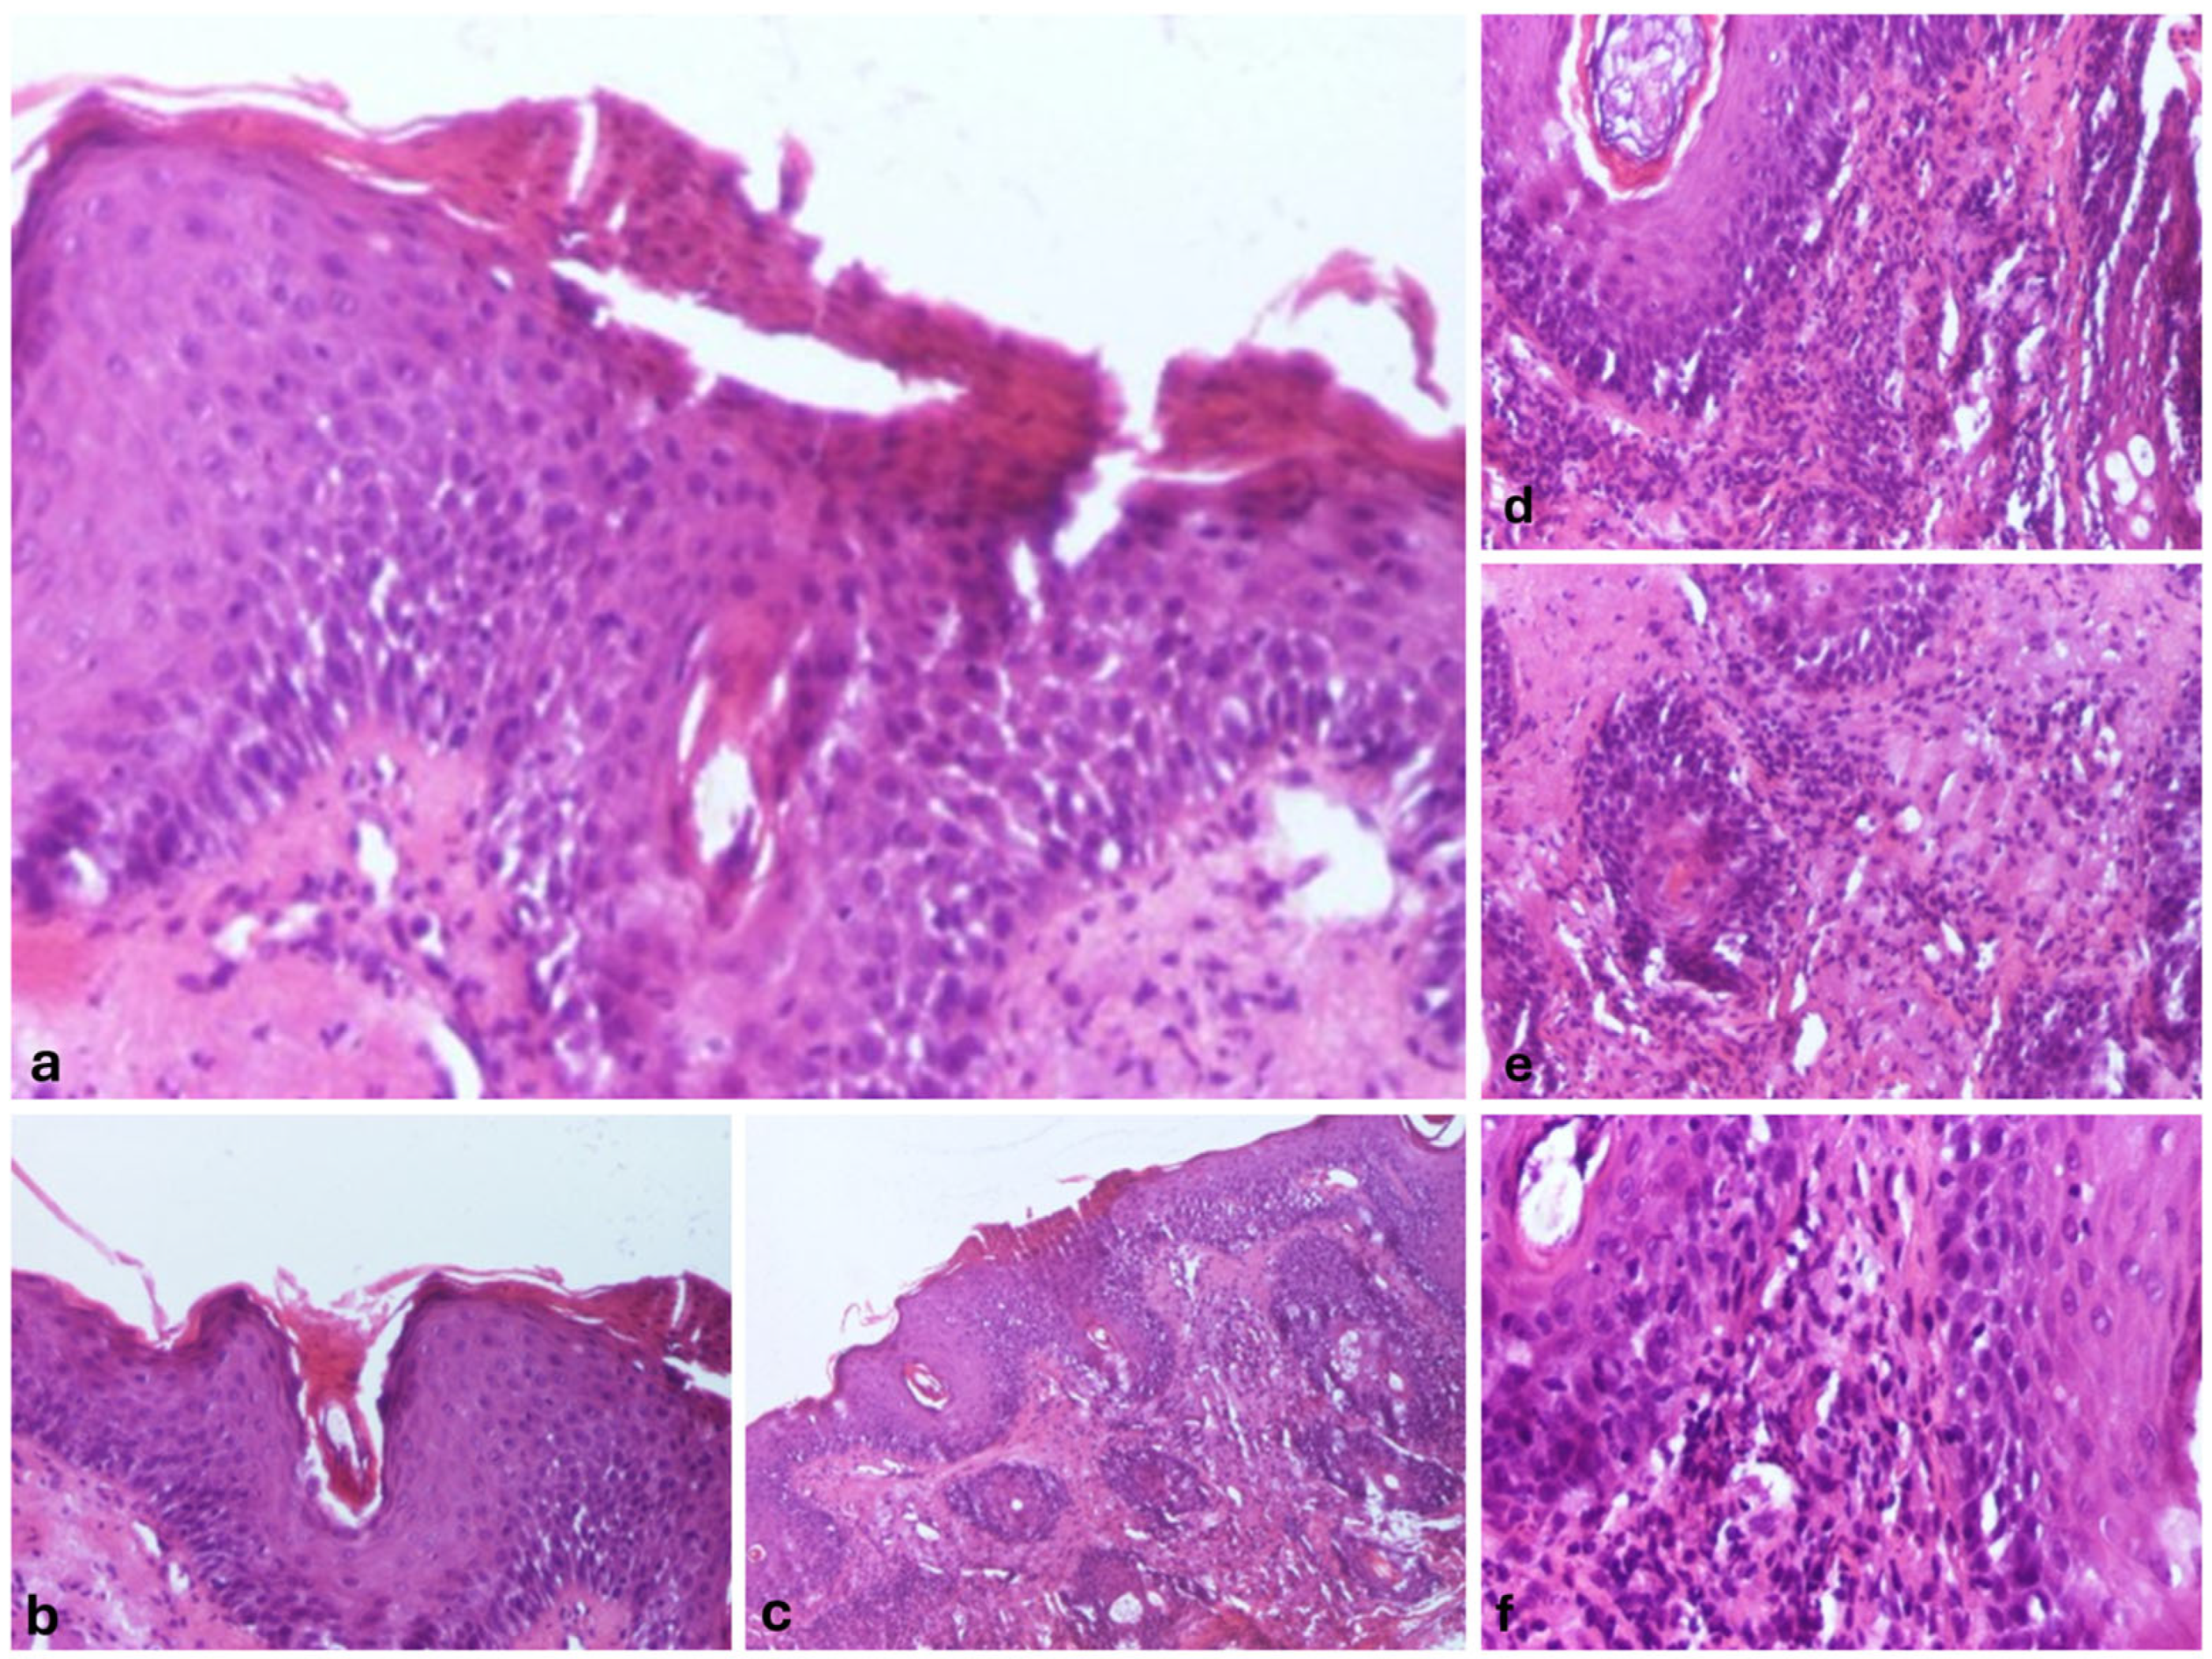

We also performed a skin biopsy (Figure 2) that revealed an ortokeratotic epidermis with focal areas of parakeratosis at the follicular openings (Figure 2a,b), irregular acanthosis, and focal spongiosis (Figure 2c). Numerous pilosebaceous follicles were observed, surrounded by a dense inflammatory infiltrate composed of lymphocytes and neutrophils, along with their infiltration into the surrounding tissue (Figure 2d–f).

Figure 2. Morphopathological features revealed the following: epidermis with orto- and parakeratosis, Hematoxylin and Eosin (HE), 100× magnification (a); follicular hyperkeratosis, with keratinous material filling the infundibulum of the hair follicles, HE, 100× magnification (b); epidermis with irregular acanthosis, and focal spongiosis, HE, 40× magnification (c); superficial perivascular and perifollicular infiltrate, primarily composed of lymphocytes, with occasional neutrophils, HE, 100× magnification (d); follicular epithelium damage with the dermal region surrounding the follicle infiltrated by a mixture of lymphocytes and neutrophils, HE, 100× magnification (e); and perivascular and perifollicular infiltrate, primarily composed of lymphocytes, with occasional neutrophils, HE, 100× magnification (f).